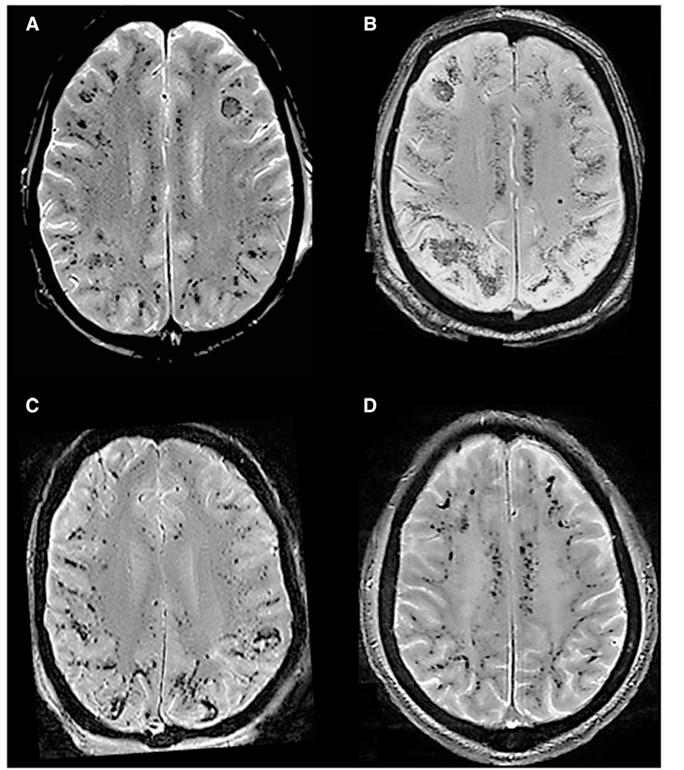

CMBs发生率和数量随着放疗时间延长而逐年增加,与放疗剂量和目标体积以及胚胎组织学呈正相关,与患者的年龄呈负相关。放疗后的CMBs以脑叶多见,且以枕叶为主。CMBs的出现与认知降落有关。

放疗 T2*WI示放疗前(A)、放疗后21个月(B)、放疗后33个月(C)、放疗后44个月(D)和放疗后62个月(E)。CMBs随时间的延长而增多。